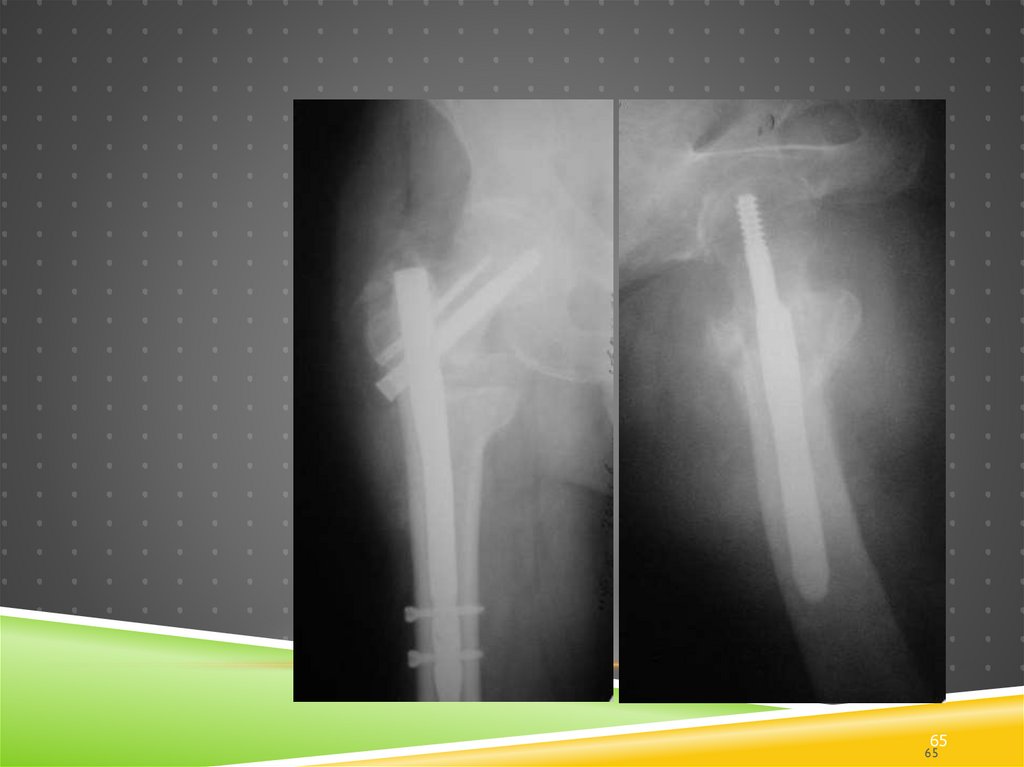

113. Ревизионный остеосинтез

РЕВИЗИОННЫЙ ОСТЕОСИНТЕЗ

В чем

проблема?

114. Ревизионный остеосинтез

Должен

исправлять

ошибки

предыдущего

этапа?

115. Ревизионный остеосинтез

Закономерный

результат

116. Ревизионный остеосинтез

Пора делать настоящий

остеосинтез?

Плюс вальгизирующая

подвертельна остеотомия

А ведь можно было просто

правильно выполнить

первичный остеосинтез!